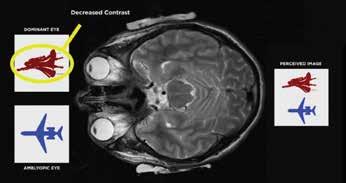

“Dichoptic therapy for amblyopia is absolutely game-changing,” he told EuroTimes. “The way it works is fascinating yet very simple, but it is a very big paradigm shift for people to understand.”

However, this is no longer the case with the advent of dichoptic treatment—a visual training process involving the presentation of simultaneous and separate visual stimuli to both eyes.

The Bynocs vision therapy software presents the contrast-adjusted images to the two eyes, with the dominant eye receiving an image of lesser contrast than the amblyopic eye. For possibly the first time ever, the brain receives an equal image from the two eyes during the therapy, encouraging it to use both eyes at the same time.

This contrast differentiation removes the interocular suppression in the ocular dominance columns in the amblyopic eye, resulting in a sustained visual gain. The neuroadaptive treatment is non-invasive, safe, and very effective, Dr Cummings said.